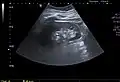

Renal cyst as seen on abdominal ultrasound